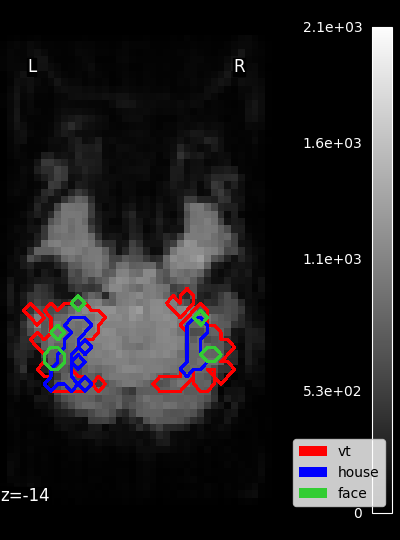

../_images/sphx_glr_plot_haxby_masks_001.png

Masks

• Masking fMRI data: To perform the analysis on some voxels only, we will provide a spatial mask of voxels to keep, which is provided with the dataset (here mask_vt a mask of the ventral temporal cortex that comes with data).